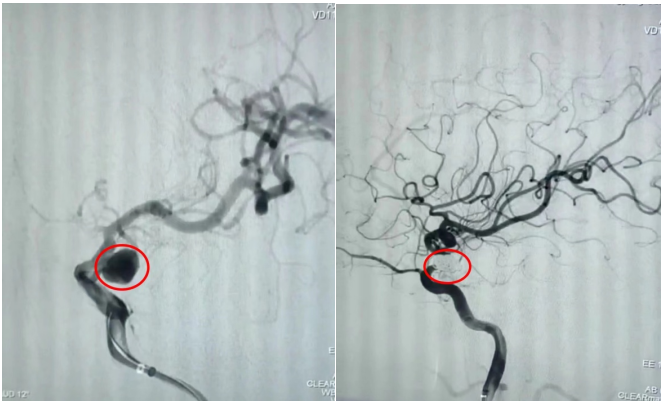

通訊員劉洋、劉立君報道: 9月2日家住衡山縣的劉爺爺從衡陽市中心醫(yī)院神經(jīng)內(nèi)科出院了。劉爺爺8月22日因左側(cè)頸內(nèi)動脈后交通段動脈瘤破裂致蛛網(wǎng)膜下腔出血,病情危在旦夕,在衡山縣人民醫(yī)院行急診全腦血管造影明確病因后,連夜轉(zhuǎn)入衡陽市中心醫(yī)院神經(jīng)內(nèi)科治療。衡陽市中心醫(yī)院神經(jīng)內(nèi)科介入團隊立即接手病人,經(jīng)過認真查看病人、細致分析病情,聯(lián)合介入室、麻醉科為病人緊急行動脈瘤介入栓塞術(shù),手術(shù)順利,術(shù)后通過腦脊液置換、預(yù)防腦動脈痙攣、預(yù)防深靜脈血栓、預(yù)防感染等綜合治療措施,緩解了劉爺爺?shù)念^痛癥狀,避免了并發(fā)癥的發(fā)生,10天后劉爺爺又回到了衡山縣人民醫(yī)院進行后續(xù)康復(fù)治療。